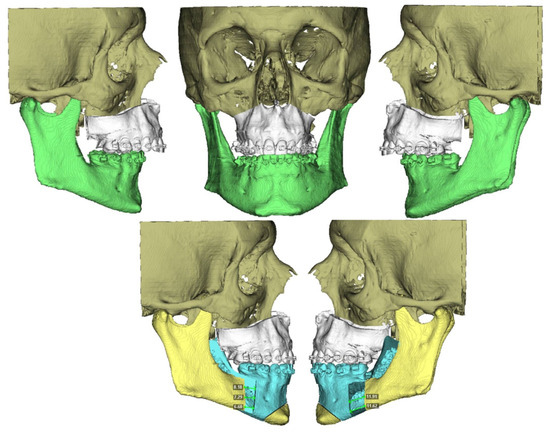

Postoperative clinical outcomes showed consistent improvements across key respiratory and subjective measures (Table 2). Descriptive and inferential analyses demonstrated significant postoperative improvements across all measured parameters. The Apnea–Hypopnea Index (AHI) decreased from a preoperative mean of 48.8 ± 23.6 to 12.4 ± 10.0 postoperatively (Z = −2.201, p = 0.035; 95% CI [0.031–0.038]). Similarly, the Epworth Sleepiness Scale improved from 14.5 ± 4.6 to 7.8 ± 2.1 (Z = −2.207, p = 0.029; 95% CI [0.026–0.033]), indicating a substantial decrease in subjective daytime sleepiness. Airway space increased from a preoperative mean of 51.8 ± 9.0 mm2 to 91.8 ± 26.6 mm2 postoperatively (Z = −2.201, p = 0.035; 95% CI [0.031–0.038]) (Figure 7). Spearman’s rank correlation analysis revealed a strong positive association between airway space enlargement and improvement in Epworth scores (ρ = 0.754, p = 0.084). This result may suggest that anatomical gains may be linked to subjective relief from daytime sleepiness. No significant correlations were found between AHI improvement and either airway change (ρ = −0.314, p = 0.544) or Epworth reduction (ρ = −0.348, p = 0.499), possibly due to the limited sample size (Table 2). None of the patients were using CPAP at 6 months post-surgery and all of them were asymptomatic.

Figure 7. Comparison of preoperative upper airway volume (A) (minimum area: 46 mm2) versus postoperative upper airway volume (B) (minimum volume: 67 mm2), showing representative volumetric improvement.